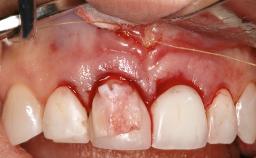

A 72-year-old female patient was referred to the specialist clinic with signs of peri-implantitis associated with implant 14. Two implants (sites 14 and 15) had been in function for three years. The patient was in good general health and was not taking any medication. She was a former smoker (12–15 cigarettes a day for 50 years) but had ceased smoking two years prior to implant placement. Her periodontal condition was stable, with no probing depths above 5 mm and a full-mouth plaque score (FMPS) of 35%.